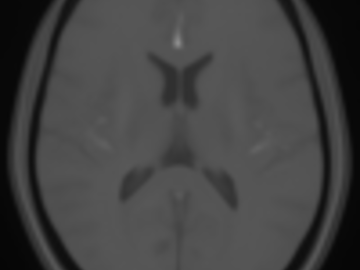

Automatic segmentation of stroke lesions in non-contrast computed tomography datasets with conv...

Non-contrast computed tomography (NCCT) is commonly used for volumetric follow-up assessment of ischemic strokes. However, manual lesion segmentation is time-consuming and subject to high inter-observer variability. The aim of this study was to develop and establish a baseline convolutional neural network (CNN) model for automatic NCCT lesion segmentation. A total of 252 multi center clinical NCCT datasets, acquired from 22 centers, and corresponding manual segmentations were used to train (204 datasets) and validate (48 datasets) a 3D multi scale CNN model for lesion segmentation. Post processing methods were implemented to improve the CNN-based lesion segmentations. The final CNN model and post processing method was evaluated using 39 out of distribution holdout test datasets, acquired at seven centers that did not contribute to the training or validation datasets. Each test image was segmented by two or three neuroradiologists. The Dice similarity coefficient (DSC) and predicted lesion volumes were used to evaluate the segmentations. The CNN model achieved a mean DSC score of 0.47 on the validation NCCT datasets. Post-processing significantly improved the DSC to 0.50 (P<0.01). On the holdout test set, the CNN model achieved a mean DSC score of 0.42, which was also significantly improved to 0.45 (P<0.05) by post processing. Importantly, the automatically segmented lesion volumes were not significantly different from the lesion volumes determined by the expert observers (P>0.05) and showed excellent agreement with manual lesion segmentation volumes (intraclass correlation coefficient, ICC = 0.88). The proposed CNN model can automatically and reliably segment ischemic stroke lesions in clinical NCCT datasets. Post processing techniques can further improve accuracy. As the model was trained and evaluated on datasets from multiple centers, it is broadly applicable and is publicly available.